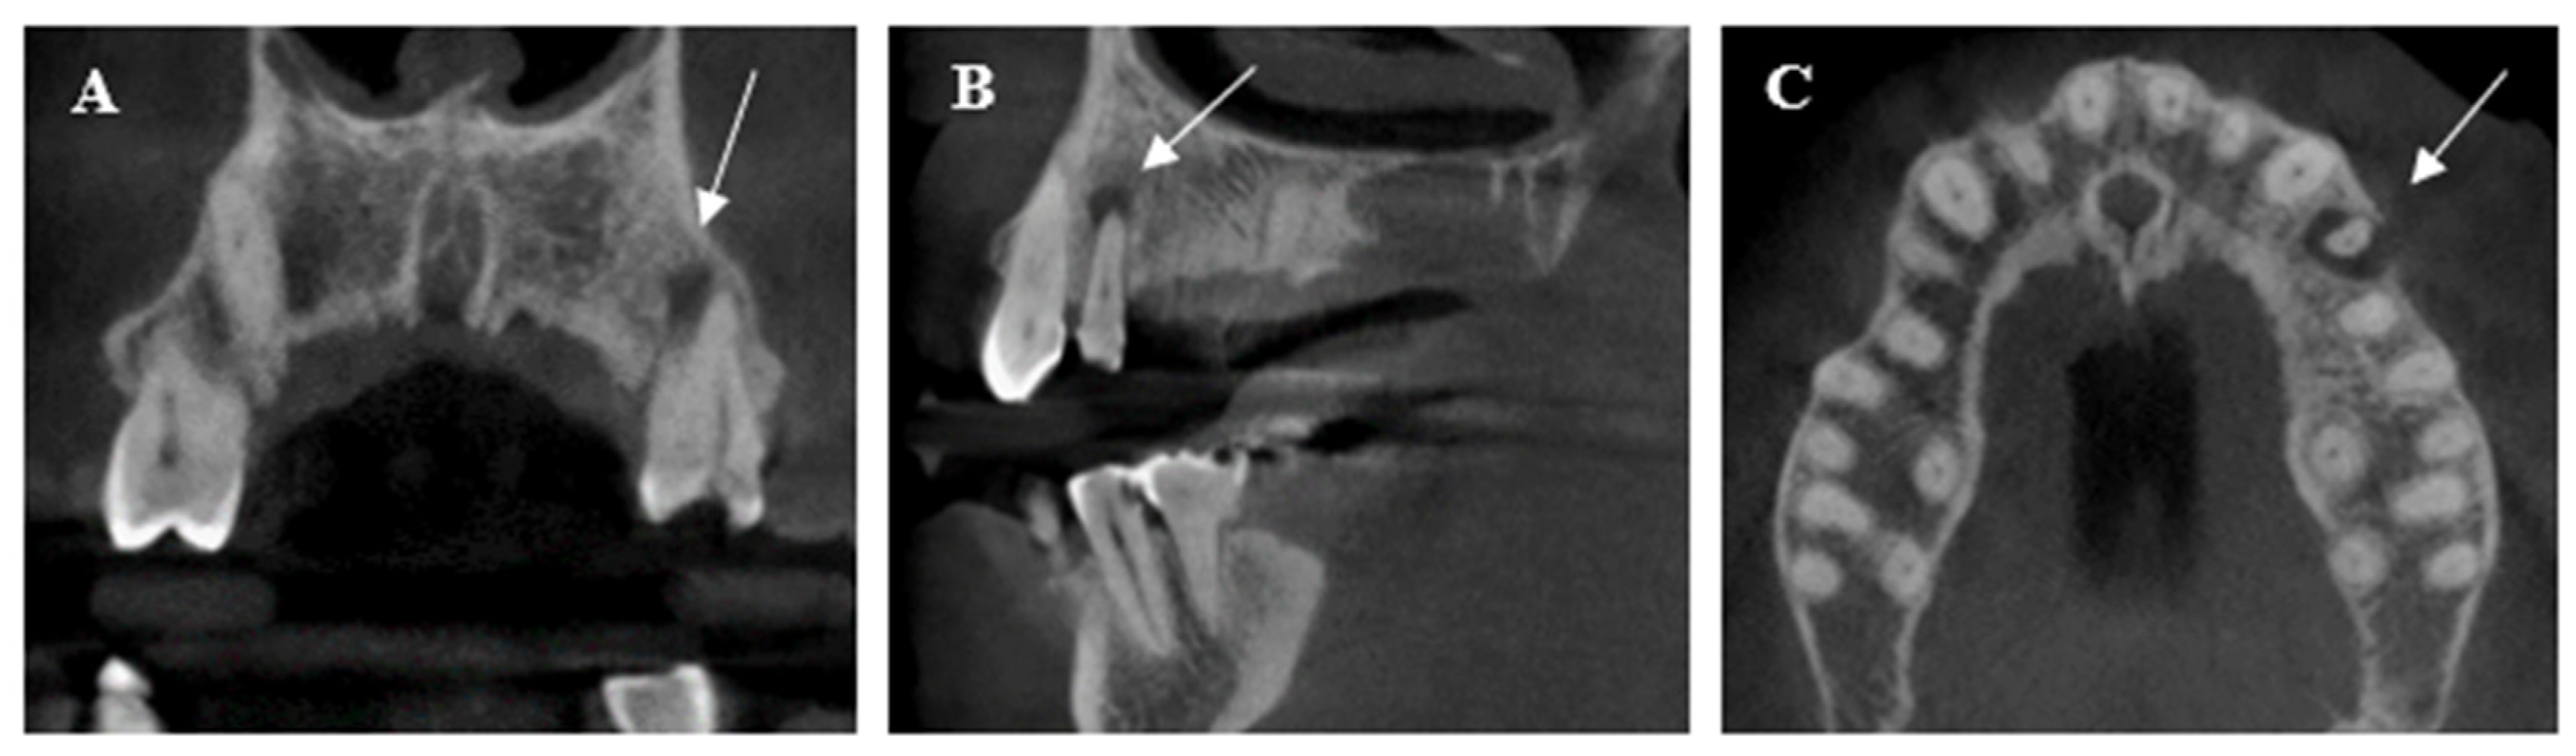

- Ali, A.H.; Mahdee, A.F.; Fadhil, N.H.; Shihab, D.M. Prevalence of periapical lesions in non-endodontically and endodontically treated teeth in an urban Iraqi adult subpopulation: A retrospective CBCT analysis. J. Clin. Exp. Dent. 2022, 14, 953–958. [Google Scholar] [CrossRef]